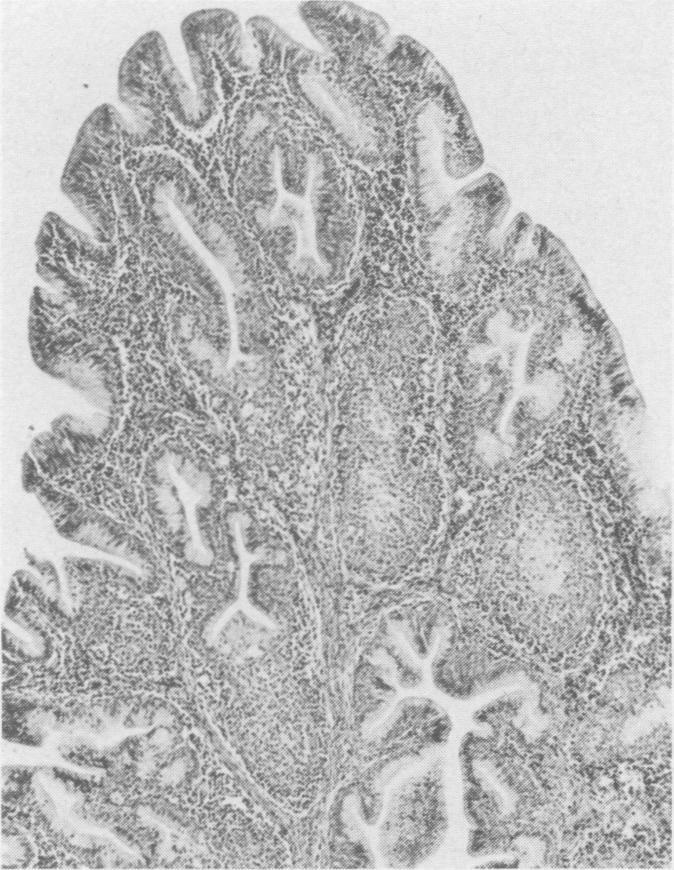

Five commercial broiler flocks, not vaccinated for infectious bursal disease virus, derived from infectious bursal disease virus-vaccinated breeder flocks were surveyed for evidence of bursal damage and infectious bursal disease virus infection. They were compared with two groups of birds raised in isolation. Serum samples from one day old chicks contained maternal anti-infectious bursal disease virus antibodies which declined to undetectable levels by four weeks of age. Serum antibody levels remained undetectable in both control groups and one commercial flock, whereas four of the five commercial flocks had actively produced anti-infectious bursal disease virus antibodies by slaughter age. The weight of bursae from infectious bursal disease virus-positive flocks declined as compared to controls after four weeks of age. The decline in weight correlated with the appearance of histopathological lesions. Infectious bursal disease virus antigen was demonstrated in selected infected bursae and infectious bursal disease bursae and infectious bursal disease virus was isolated from some of these damaged bursae. Clinical infectious bursal disease was not observed in any of the commercial flocks. The importance of subclinical bursal damage and immunosuppression is discussed.

对五群未接种传染性法氏囊病病毒疫苗、来自接种过传染性法氏囊病病毒疫苗的种鸡群的商品肉鸡进行了调查,以寻找法氏囊损伤和传染性法氏囊病病毒感染的证据。将它们与两组隔离饲养的鸡进行比较。一日龄雏鸡的血清样本含有母源抗传染性法氏囊病病毒抗体,这些抗体在四周龄时降至无法检测的水平。在两个对照组和一群商品肉鸡中,血清抗体水平一直无法检测到,而五群商品肉鸡中有四群在屠宰时已主动产生了抗传染性法氏囊病病毒抗体。四周龄后,传染性法氏囊病病毒阳性鸡群的法氏囊重量与对照组相比有所下降。重量的下降与组织病理学损伤的出现相关。在选定的受感染法氏囊中检测到了传染性法氏囊病病毒抗原,并且从其中一些受损法氏囊中分离出了传染性法氏囊病病毒。在任何一群商品肉鸡中均未观察到临床传染性法氏囊病。文中讨论了亚临床法氏囊损伤和免疫抑制的重要性。